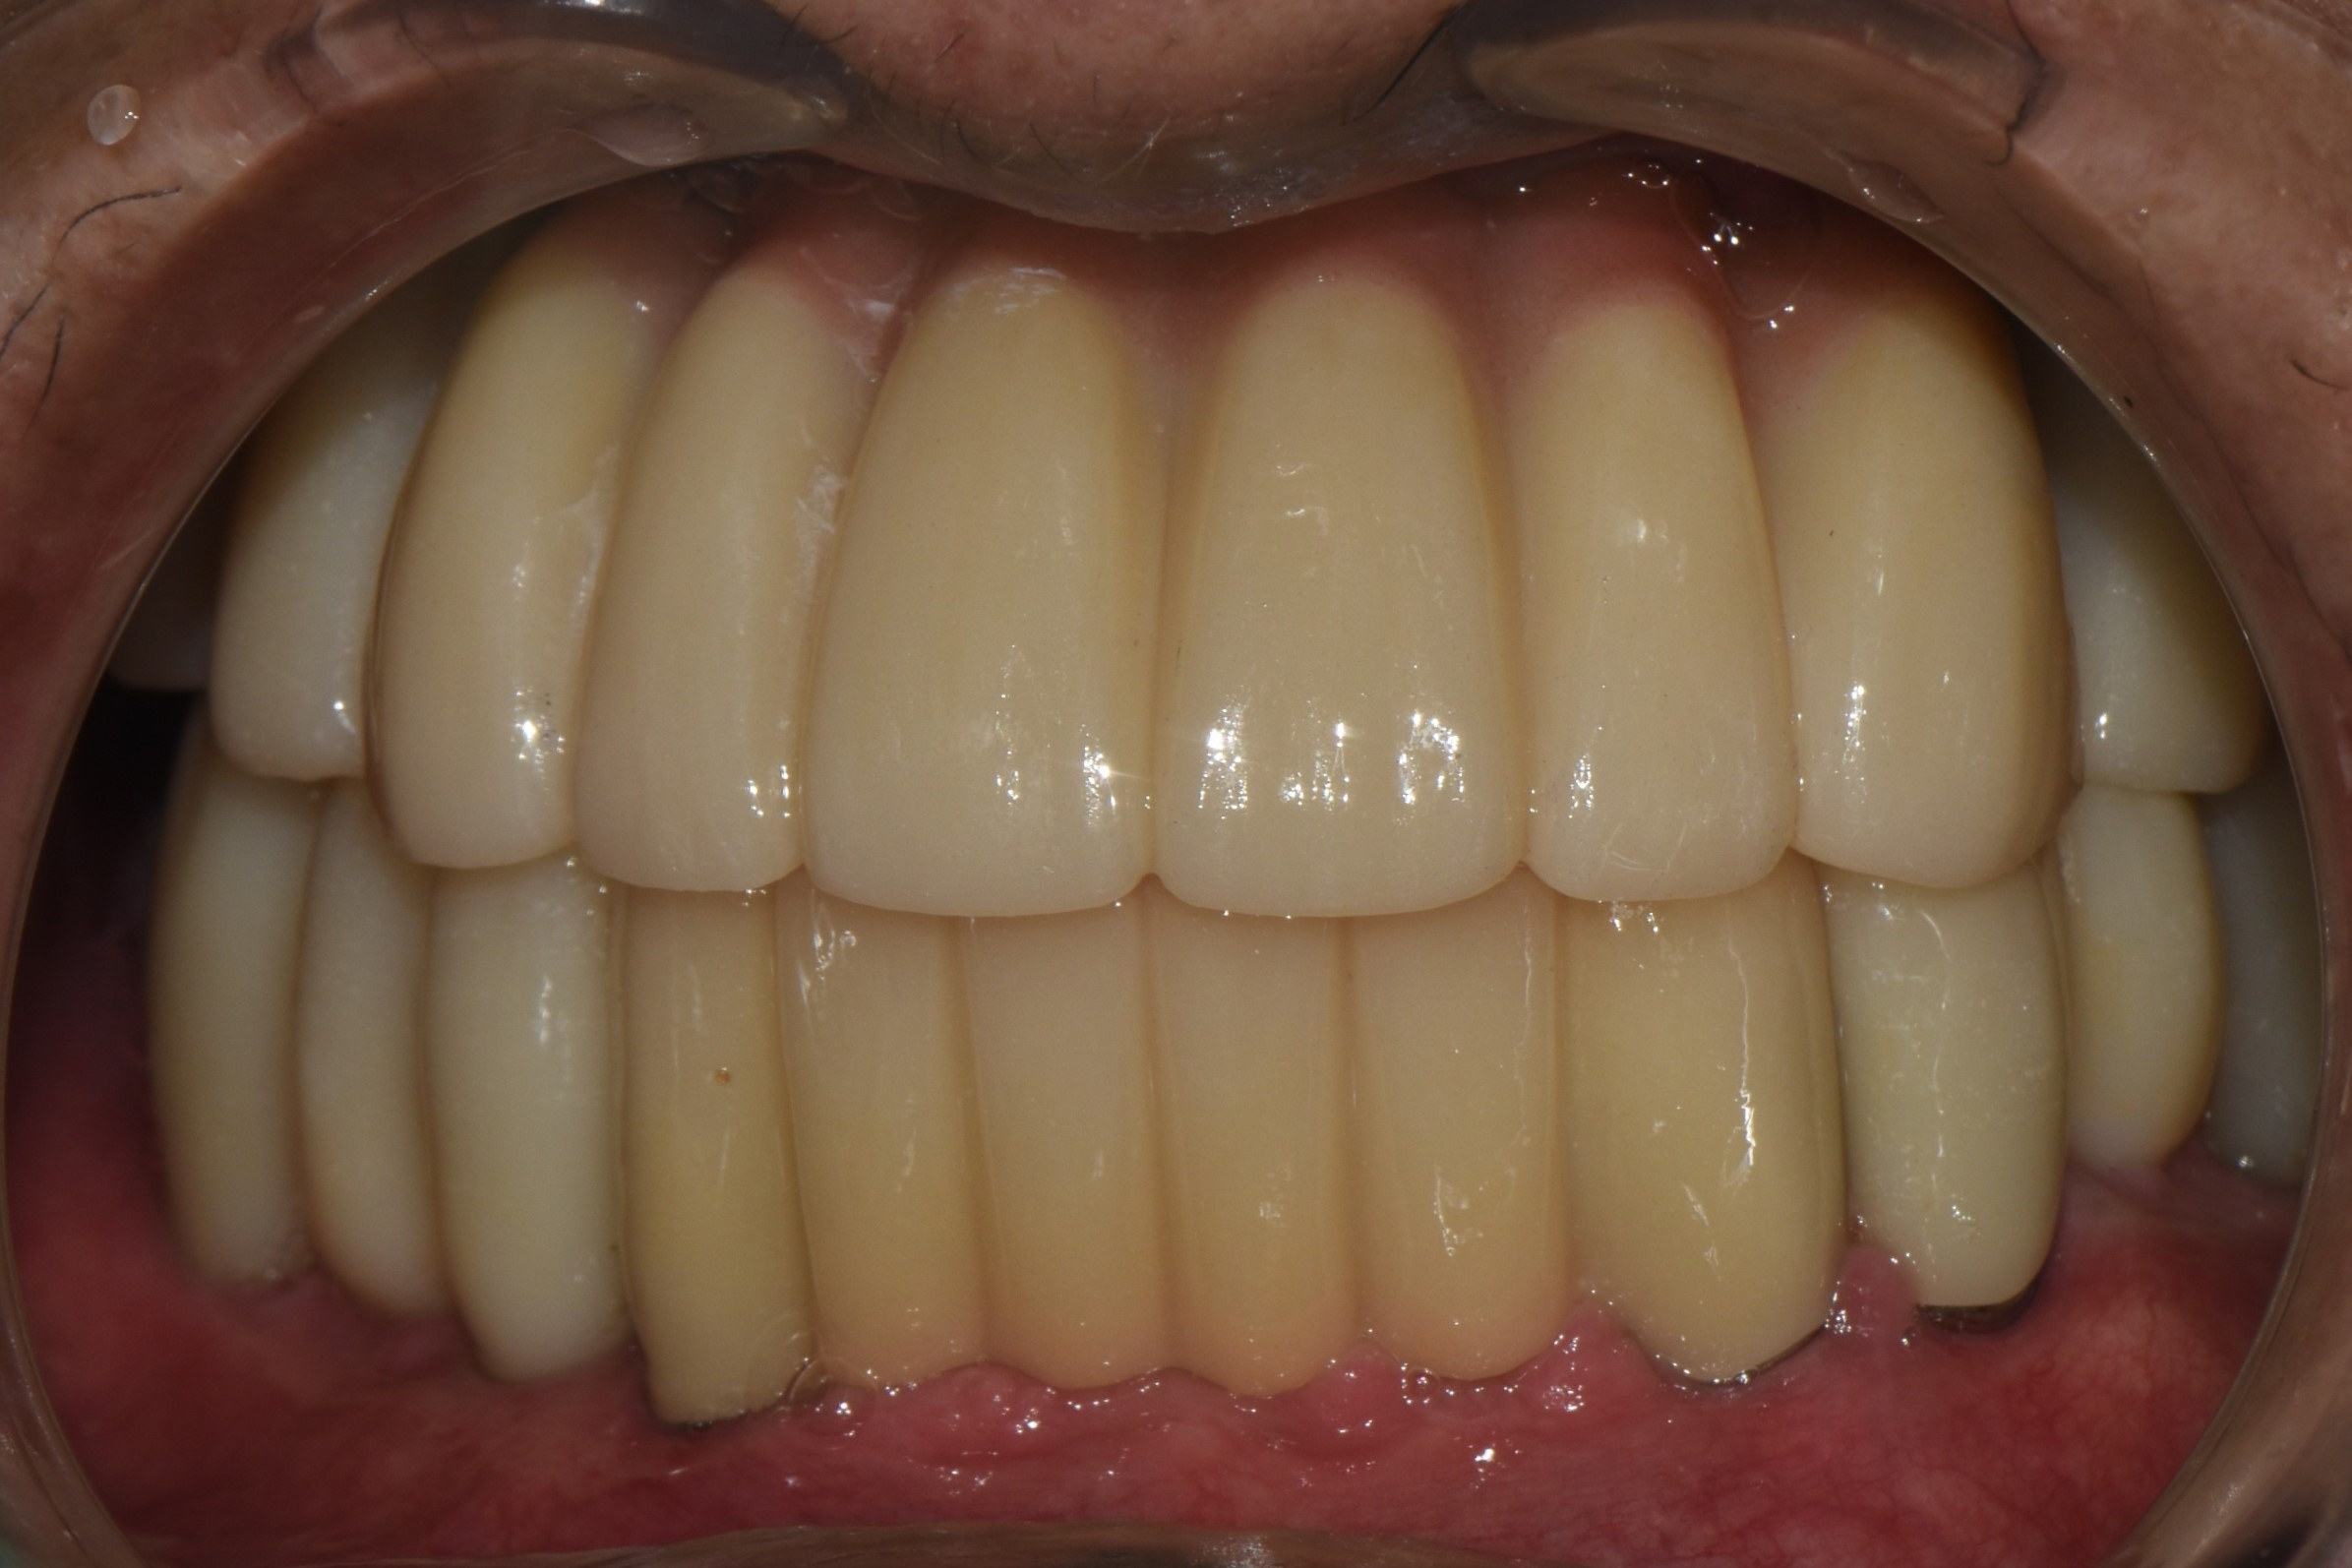

비강거상과 상악동거상을 동반한 전체임플란트 치료 증례 2026-02-20 hit.70 |

촬영일시: 2024.05.03

[ 치료기간: 2024년 05월 03일 ~2025년 03월 14일 ] ※ 365서울앞선치과의원의 모든 컬럼은 각 진료과 의료진이 직접 작성합니다. 365서울앞선치과의원 임상 케이스 게시물은 환자분께 의학적으로 정확하고 상세한 정보를 드리기 위해 각 진료과 의료진이 직접 작성하며, 모든 증례 사진은 본원 의료진이 직접 시술한 증례를 촬영한 것으로, 의료법 제23조, 제56조에 의거하며 환자분의 동의를 얻어 포스팅에 사용하였습니다. 또한 해당 케이스는 본 환자분의 치료 결과이며, 환자 상태에 따라 치료의 결과는 달라질 수 있습니다. |